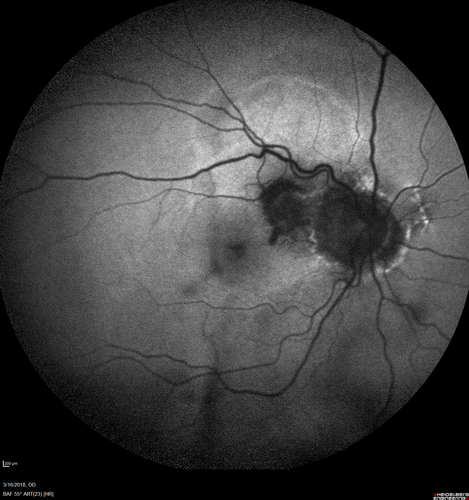

Juxtapapillary CNVM - Hemorrhage

83 year old female VA 20/200 improved to 20/32 within 2 months with Lucentis

Juxtapapillary CNVM with Hemorrhage - Lucentis